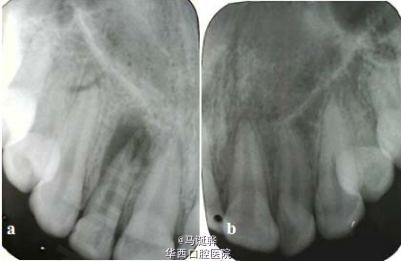

越来越逆天的侧切牙

伴随着越来越多的侧切牙双根管被大家发掘,大家对这个小牙齿是不是有点胸有成竹。但是,道高一尺魔高一丈,侧切牙也越来越不让人省心了。